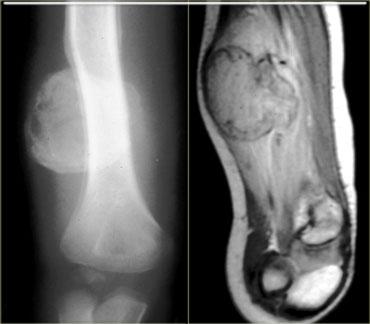

Hoại tử cơ vôi hóa là một tình trạng hiếm gặp sau chấn thương, đặc trưng bởi sự hình thành muộn của một khối vôi hóa loạn dưỡng, xảy ra hầu như độc quyền ở chi dưới.

Trong hoại tử cơ vôi hóa, toàn bộ một cơ đơn lẻ bị thay thế bởi một khối hình thoi với phần trung tâm hóa lỏng và vôi hóa ngoại vi.

Chúng có thể biểu hiện như các khối mô mềm ngày càng to lên với các đặc điểm lâm sàng gợi ý một khối u mô mềm đang phát triển hoặc nhiễm trùng.